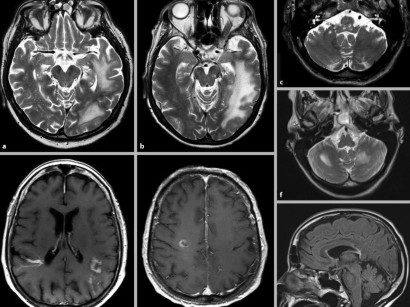

Herz Mrt Zur Diagnostik Der Kardialen Amyloidose Bedeutung Des T1 Mappingcardiac Mri For Evaluating Cardiac Amyloidosis Importance Of T1 Mapping Request Pdf , Ein dringender verdacht auf das vorliegen einer kardialen amyloidose ergibt sich aus den charakteristischen echokardiographischen befunden und dem ekg.

Herz Mrt Zur Diagnostik Der Kardialen Amyloidose Bedeutung Des T1 Mappingcardiac Mri For Evaluating Cardiac Amyloidosis Importance Of T1 Mapping Request Pdf . Kardiale Amyloidose Führt Zu Einer Verdickung Des Herzmuskels Und Zu Einer Versteifung Des Herzens, Was Vor Allem Die Füllfunktion Sehr Beeinträchtigt.